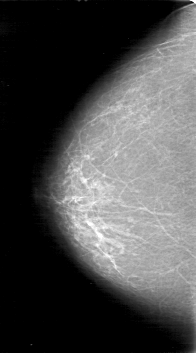

D_4047_1.LEFT_MLO

RIGHT_CC LINES 5281 PIXELS_PER_LINE 2926 BITS_PER_PIXEL 12 RESOLUTION 43.5 NON_OVERLAY